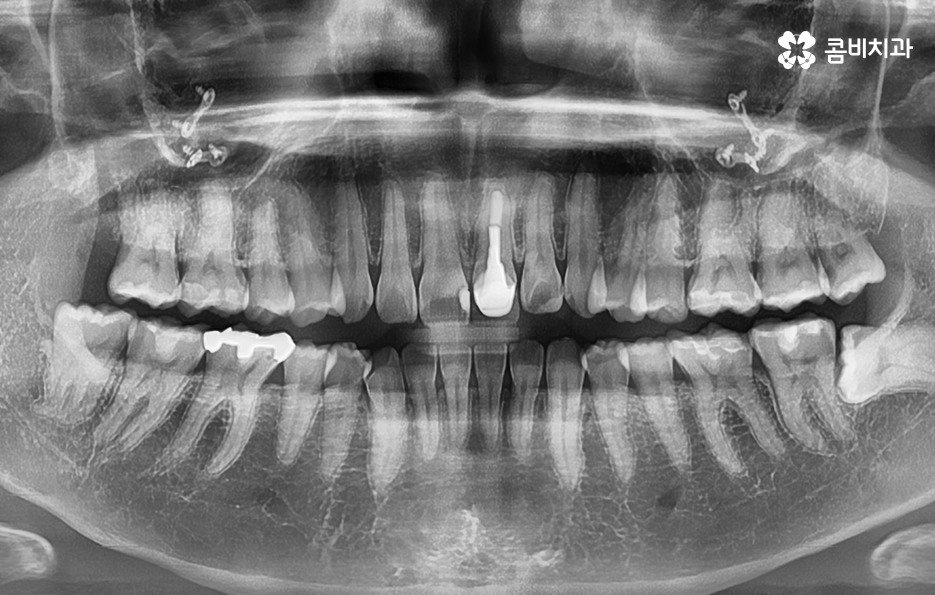

20살이 지났지만 사랑니가 안나고 있다고 생각하는 분들도 있지만 오히려 사랑니가 나올 공간이 부족하여 매복된 상태로 자라고 있는 경우가 많기 때문에 사랑니의 상태 체크를 위해 꼭 성인이 되신 분들은 사랑니의 확인을 위해서라도 꼭 검진을 받아보시길 바라며 매년 주기적으로 검진과 스케일링을 권하고 있는데요

현대인들은 사랑니의 위치가 좋지 않아서 주변 치아와 잇몸에 염증이 발생되는 사례가 많고 특히 하악에 매복 사랑니가 있는 경우가 많은데 완전히 누워서 자라는 사랑니는 발치 자체도 어렵지만 뿌리가 깊어지기 전에 발치하는 것이 발치나 회복에도 수월하기 때문에 정확한 사랑니 발치 시기의 골든타임을 놓치지 않기 위해서도 사랑니가 나올 무렵에 자신의 사랑니가 어떻게 자라고 있는지 확인하실 필요가 있어요